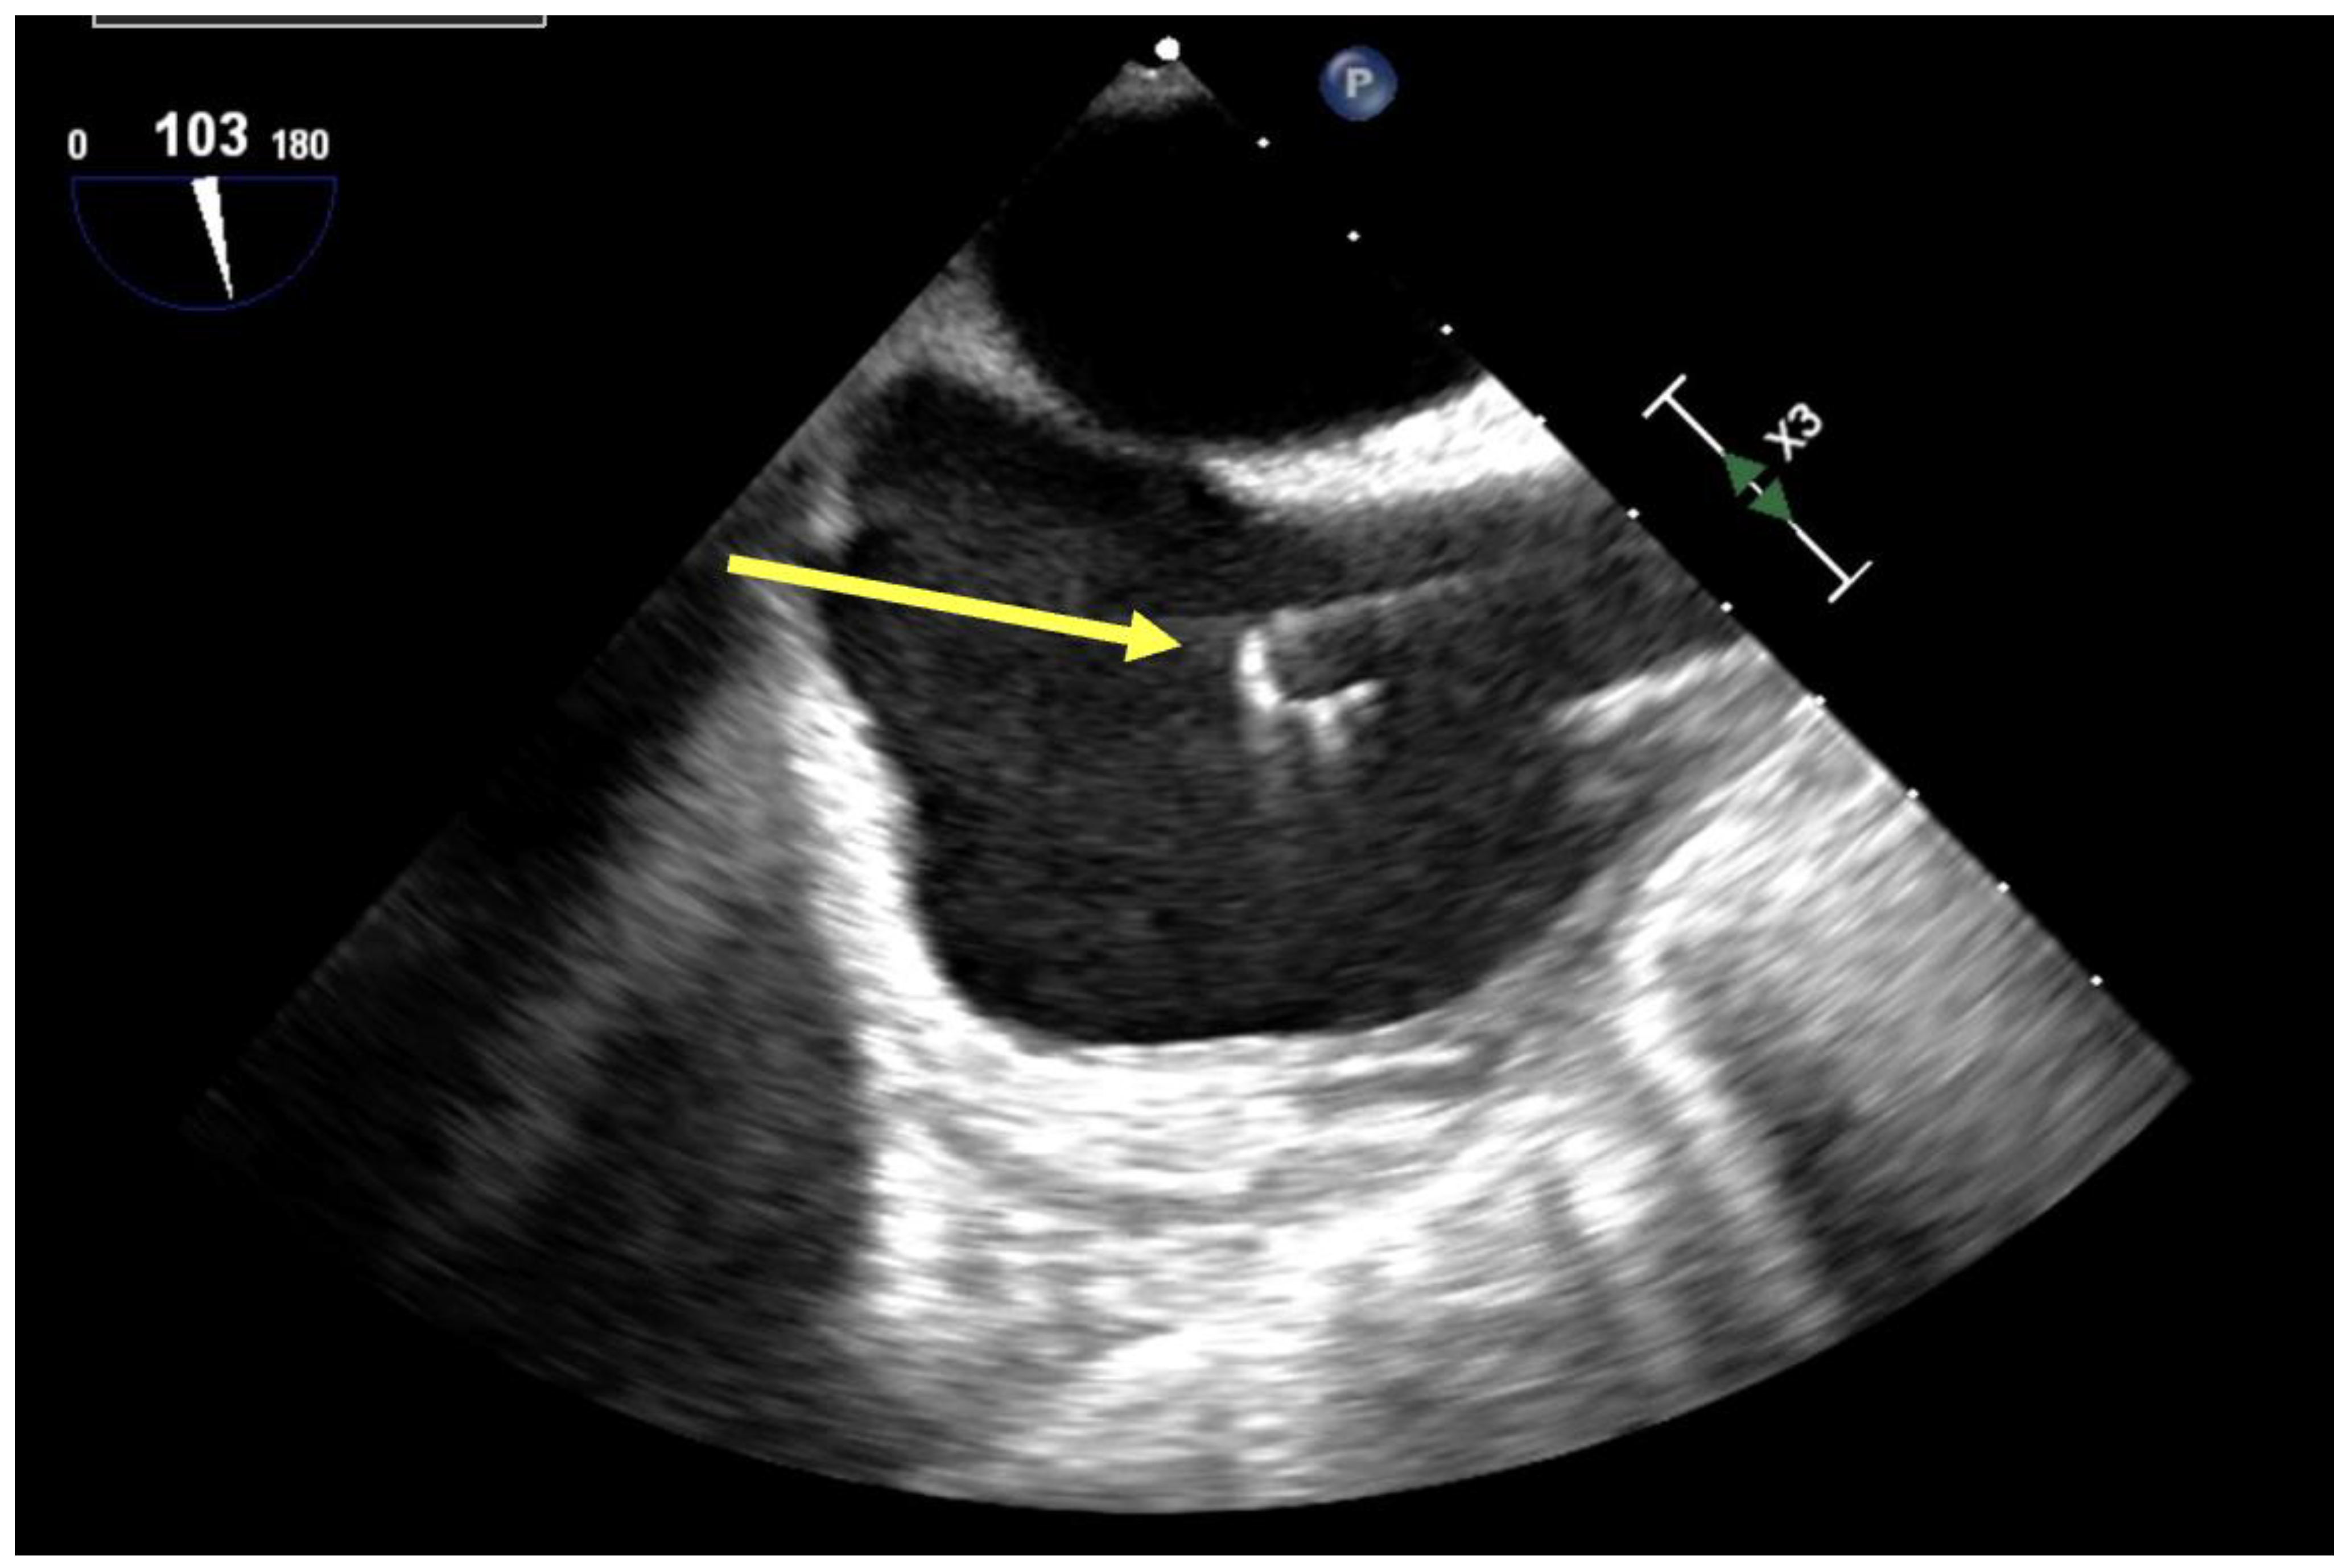

- Cha, S.; Kim, B.S.; Ha, J.S.; Bush, E.L. How to do it: A safe bedside protocol for dual-lumen right internal jugular cannulation for venovenous extracorporeal membrane oxygenation in COVID-19 patients with severe acute respiratory distress syndrome. ASAIO J. 2022, 69, 31–35. [Google Scholar] [CrossRef] [PubMed]